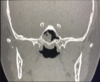

DESCRIBE ESTA TAC Y DX

* se observa una imagen de ocupación en el seno maxilar derecho 90-95%, homogéneo, imagen de ocupación de 50-60% en el piso, paredes * sinusitis etmoidal * desviación de septum * cornetes inferiores hipertróficos * hemipaladar izq está **más alto** que el derecho y muy **cóncavo** = **estigma de que el px es respirador bucal crónico** **DX = Sinusitis maxiloetmoidal bilateral con desviación septal hacia la derecha e hipertrofia turbinal anterior**